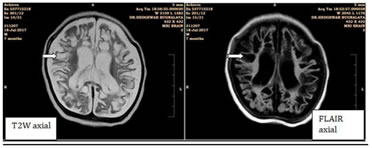

In our study, mesial temporal scleros is was found in 2 patients. Among them, hip pocampalatrophy and secondary changes (temporal horn dilatation) were present

1

Figure 1: A case of left mesial temporal sclerosis. FLAIR coronal images shows hyperintensity in left hippocampus and corresponding altered morphology of left hippocampus on TIW inversion recovery.

in both patients. Loss of hippocampal architecture and hippocampal T2, FLAIR hyperintensity were present in both patients (100%). Persistent peritrigonalhyperintensities on T2W and FLAIR images were present in one patient and chronic ischemic foci in bilateral cerebellar, occipital parenchyma and periventricular white matter were present in one patient. Malformations of cortical development constituted 11 patients presenting with seizures. Out of them, Focal cortical dysplasia (FCD) was seenin8patients (72.7%). Corpuscallosaldysgenesis/agenesis(CCD/CCA), polymicrogyria and heterotopia constituted 3 patients (27.3%) each. Pachygyria and hemimegalencephaly (HMEG)constituted 2 patients (18.2%)while microcephaly constituted there mainder with1patient(9.1%). Five patients had multiple pathologies. One had unilateral perisylvian cortical dysplasia with polymicrogyria (Congenital unilateral perisylvian syndrome). One had Joubert syndrome, heterotopia and pachygyria. One patient had heterotopia, corpus callosum dysgenesis, focal corticaldysplasia and hypoxic is chemicencephalopathy. One patient had heterotopia, polymicrogyria, corpus callosum dysgenesis and hemimegalencephaly (HMEG). One patient had hemimegalencephaly (HMEG), agyria-pachygyria with polymicrogyria. Thus, Focal cortical dysplasia (FCD) was the most common pathology in patients with malformations of cortical development.